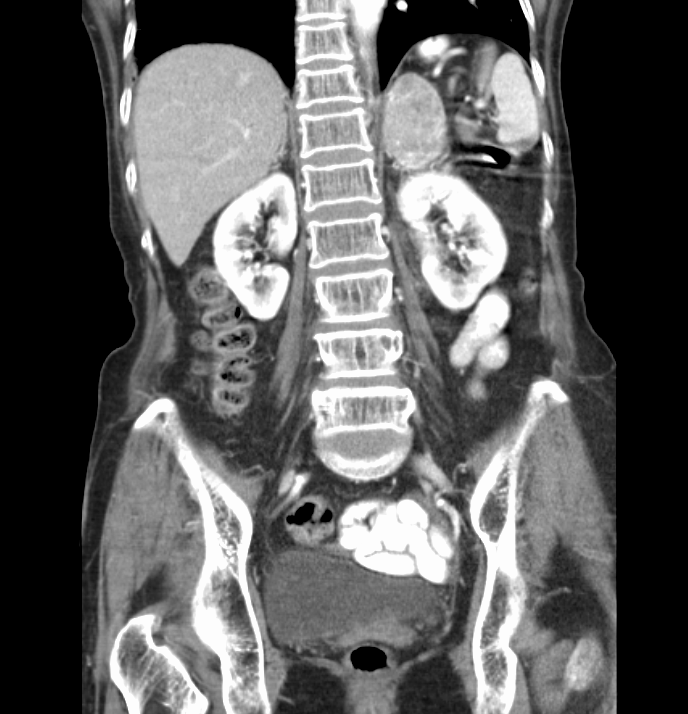

The patient is a 74 year-old African-American female with a history of hypertension, coronary artery disease status post drug-eluting stent ×1, former cigarette smoker, and iron deficiency anemia presenting with left-sided vision loss. Patient states that approximately two days ago  she woke up with painless peripheral vision loss of her left eye only. She describes it as darkness in the lateral portion of her left eye. She  reports that her vision returned to baseline throughout that day; only to return when she awoke the next morning. Since that time she endorses persistent vision loss in the left periphery. She denies blurry vision, eye pain, headaches, recent trauma, flashes, and floaters. Furthermore, she also denies dizziness, numbness weakness, dysarthria, dysphagia, fever, chills nausea, vomiting, chest pain, shortness of breath, and palpitations. She reports adherence to her antihypertensive and anti-platelet medications...